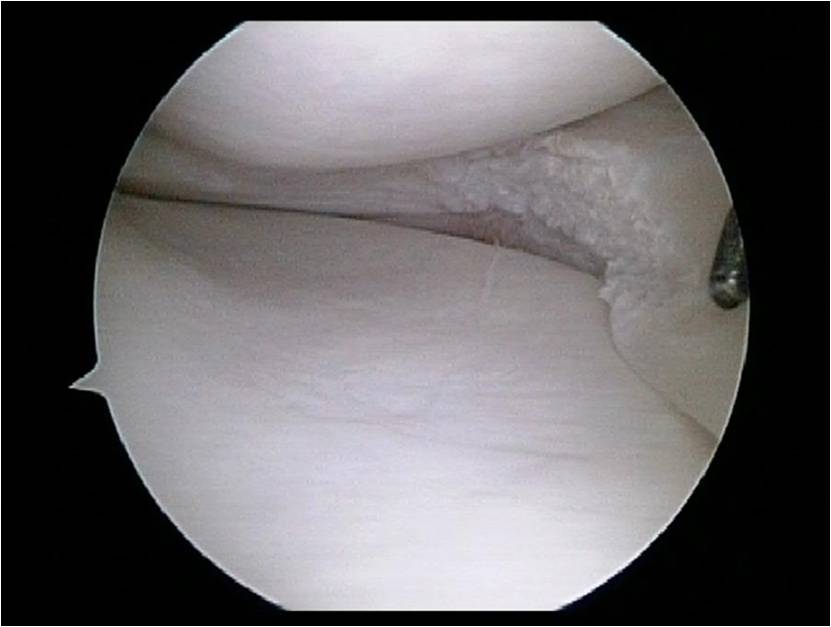

Meniscus tear

By Sujit Jos | Published July 3, 2015 | Full size is 831 × 627 pixels